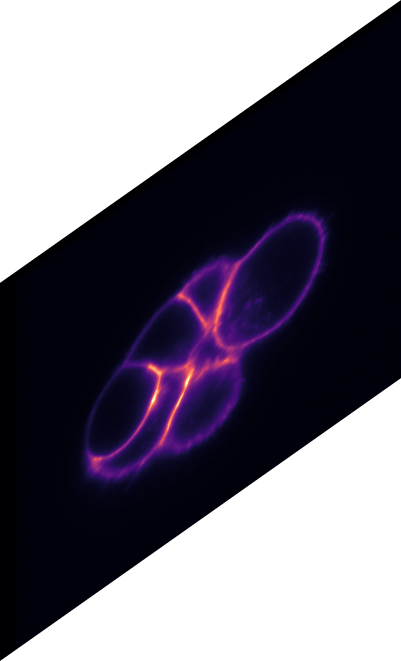

\text{Qualitative Results}